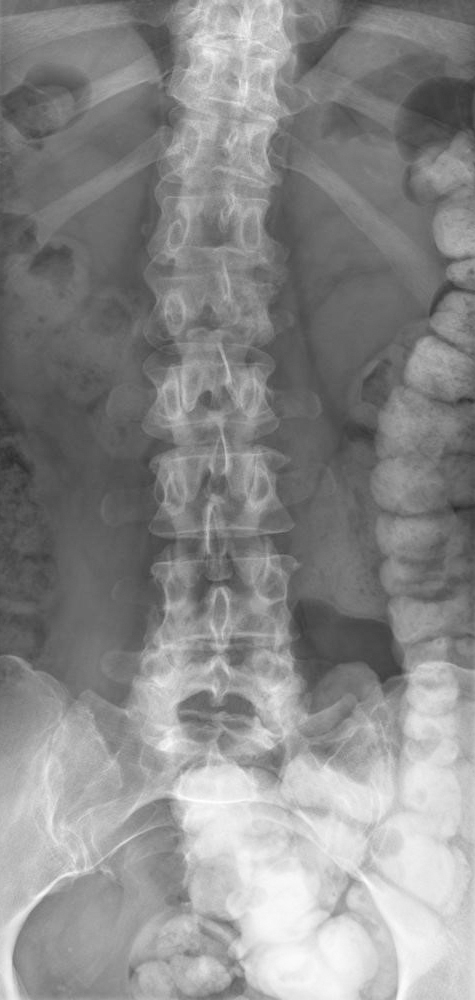

Son médecin traitant lui a prescrit de faibles doses de morphine, ce qui la soulage, et a fait réaliser l’élément suivant.

Question 11 - Concernant le tableau de la patiente (une ou plusieurs réponses exactes) :

Il s’agit d’un effet indésirable connu des inhibiteurs de l’aromatase, mais la perte du pédicule latéral gauche de L2 (vertèbre borgne) est en faveur d’une récidive.

L’aspect de vertèbre borgne est hautement évocateur d’une récidive (envahissement du pédicule latéral).

L’aspect de vertèbre borgne est fortement évocateur d’une récidive tumorale.

On doit compléter le bilan par une IRM afin de préciser les lésions rachidiennes, préciser le risque neurologique et discuter d’un geste à visée antalgique (chirurgie, radiothérapie, cimentoplastie…).

On doit également réaliser un bilan d’extension (TEP-scan ou scintigraphie osseuse et scanner thoraco-abdomino-pelvien [TAP]), afin de préciser l’étendue d’une probable récidive, et préciser la lésion à biopsier.